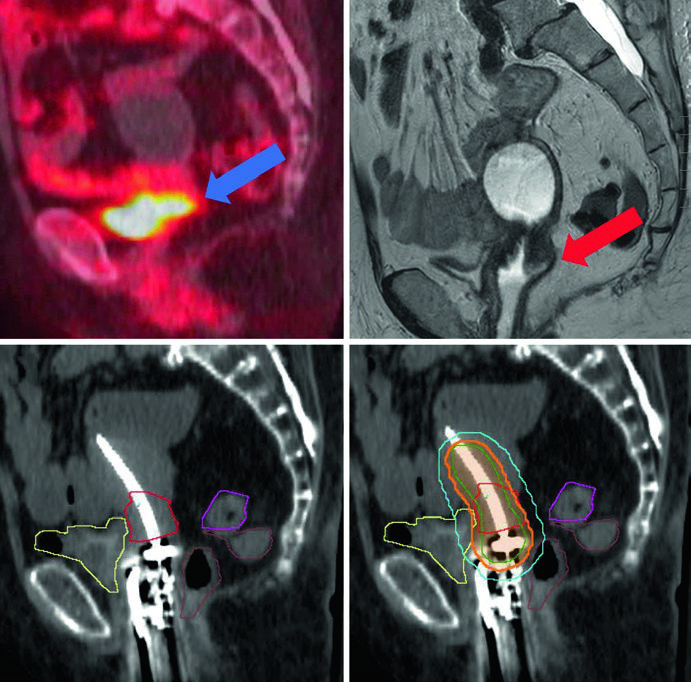

Delineamento de Volumes e Planejamento Cervical

O delineamento exige precisão absoluta. A TC de cortes finos ou RM com aplicador é mandatória para planejamento 3D. O tandem deve estar posicionado no colo e útero — se usar anel, deve ficar rente ao colo; se usar ovoides, o tandem deve bissetar os ovoides. A tamponagem vaginal não pode deslocar o anel ou os ovoides.

Os volumes-alvo seguem a terminologia GEC-ESTRO. O GTV corresponde ao tumor macroscópico visível na RM no momento da braquiterapia. O HRCTV engloba o GTV, colo uterino e extensão macroscópica ou envolvimento parametrial ao tempo do implante. O IRCTV adiciona 1 cm de margem ao HRCTV e pode incluir a extensão da doença ao diagnóstico — usado mais na Europa do que nos EUA.

Quando se utiliza TC para planejamento, os volumes-alvo tendem a superestimar a extensão da doença. A RM permite definir o GTV com muito mais acurácia. Para câncer cervical pós-operatório com margem vaginal positiva, trata-se o terço superior da vagina.